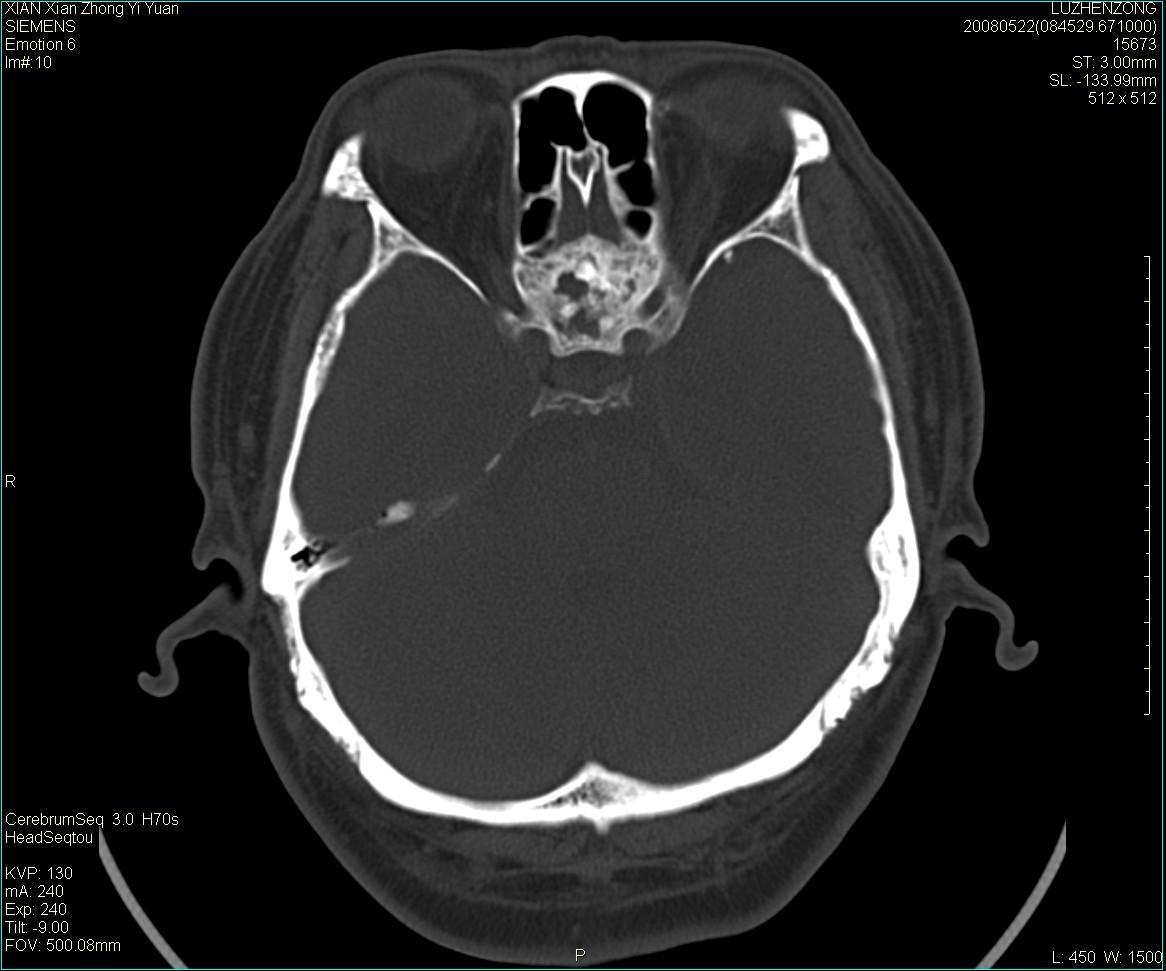

以下是引用gaoshengjiang在2008-5-28 19:06:00的发言:[br]考虑来源于蝶骨前床突区骨软骨瘤。

以下是引用卜一在2008-5-28 20:46:00的发言:[br]中颅窝“骨纤维异常增殖症”。不除外考虑来源于蝶骨前床突区“骨软骨瘤”。[br]

以下是引用liangshusheng在2008-5-28 20:13:00的发言:[br]单骨病变,考虑骨化性纤维瘤。